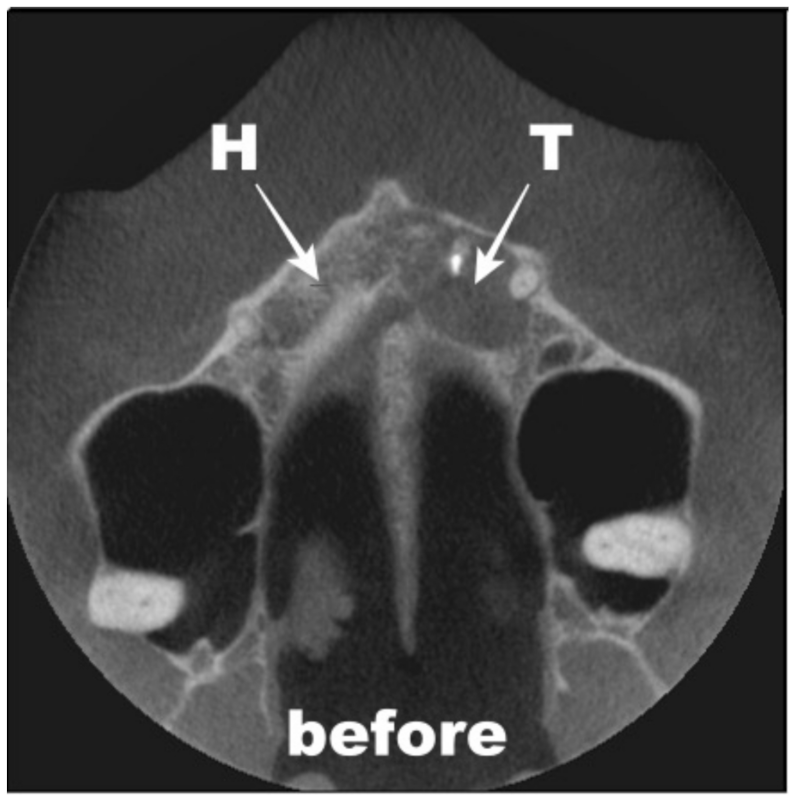

4. Results